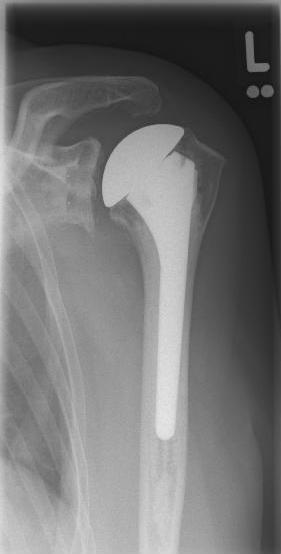

Abbildung6Conventional stem prostheses for omarthrosis and acetabular wear

left: X-ray image of a shaft prosthesis

right: anatomical shoulder prosthesis with glenoid replacement (Affinis type, Mathys company)